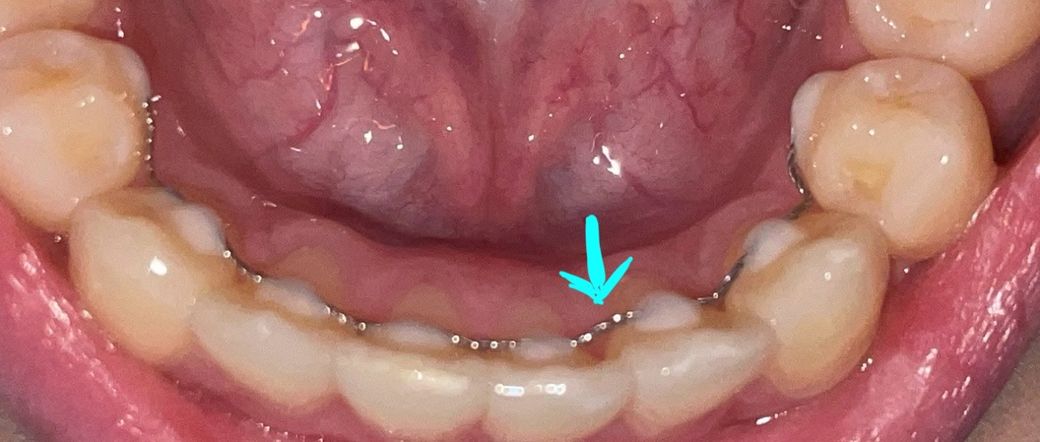

안녕하세요! 교정 끝난 지 두 달? 정도 되었는데, 얼마 전 부착해두었던 고정식 유지장치 중 일부가 약간 바깥쪽으로...? 들떠있는 걸 발견했습니다. 제가 알기로는 철사가 치아 굴곡에 맞게 부착되어 있어야 한다고 알고 있는데 아닌가요? ㅠㅠ 사소한 문제가 아닐지, 치과 예약해도 될지 궁금합니다....

고정식 유지장치가 위 사진과 같이 붙어있다고 하여 문제가 되는 부분은 없습니다. 굳이 안가보셔도 됩니다.

굴곡에 맞추어 제작되므로 최대한 틈이

없긴 하지만 레진으로 붙인

곳을 제외한 곳은 떠있기 때문에 변형이 되기도 하는데요. 해당 부위가 불편하다면 예약하고 한번 보시는게

좋습니다.

치아 모양에 맞게 제작을 하게됩니다. 아마 치아 가 약간 안쪽으로 튀어 나와서 그렇게 만들엇을 가능성과 저부위에 레진이 떨어졋을 가능성도 잇으니 일단 치과에 가셔서 체크를 받아보세요.

유지장치의 목적은 완전히 패시브하게 힘이 주어지면서 치아가 이동하지 못하도록 하는 것입니다.

일반적으론 치아 표면에 고르게 밀착해있는 것이 맞으나 상황에 따라 적절히 대처했을 수도 있습니다. 한번 체크겸 치과가보시는 것도 좋겠습니다.

고정식 유지 장치를 접착하고 있는 레진이 탈락되었다면 해당 지하를 유지해주지 못하고 있는 것입니다.

이런 경우에는 레진을 이용해서 다시 부착을 해줘야 됩니다. 치아를 유지장치가 부착되어 있지 않게 되면 치열이 어긋나게 되어 나중에 추가적인 교정이 필요할 수 있습니다.

자세한 확인을 위해서 교정 치과에서 진료를 받아보는 것을 권유드립니다.